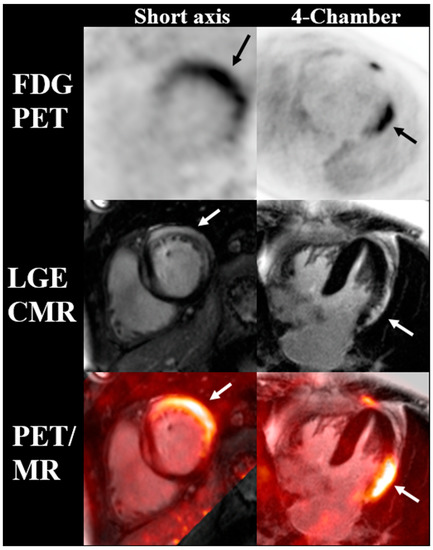

- Rischpler, C.; Rassaf, T.; Umutlu, L.; Herrmann, K.; Schlosser, T.-W.; Totzeck, M. Imaging the Inflammatory Response in Checkpoint Inhibition Myocarditis. J. Nucl. Med. 2021, 63, 14–16. [Google Scholar] [CrossRef]

- Nensa, F.; Kloth, J.; Tezgah, E.; Poeppel, T.D.; Heusch, P.; Goebel, J.; Nassenstein, K.; Schlosser, T. Feasibility of FDG-PET in myocarditis: Comparison to CMR using integrated PET/MRI. J. Nucl. Cardiol. Off. Publ. Am. Soc. Nucl. Cardiol. 2018, 25, 785–794. [Google Scholar] [CrossRef]